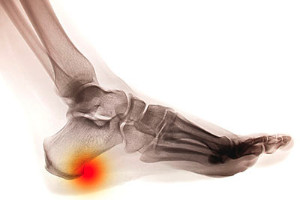

A painful condition that is known as a heel spur can occur as a result of a calcium deposit that forms between the heel and the arch. This appears to be a bony growth and can cause severe pain and discomfort. The symptoms that often accompany this condition can consist of swelling in the heel and surrounding areas, and it may be painful to walk. This ailment can be caused by obesity, shoes that do not fit correctly, or medical conditions such as arthritis. Patients who are afflicted with a heel spur may find mild relief when the affected foot is elevated, which may help to reduce existing swelling. If you have developed a heel spur, it is advised that you seek the counsel of a podiatrist who can help you to properly treat this condition.

Heel spurs are formed by calcium deposits on the back of the foot where the heel is. This can also be caused by small fragments of bone breaking off one section of the foot, attaching onto the back of the foot. Heel spurs can also be bone growth on the back of the foot and may grow in the direction of the arch of the foot.